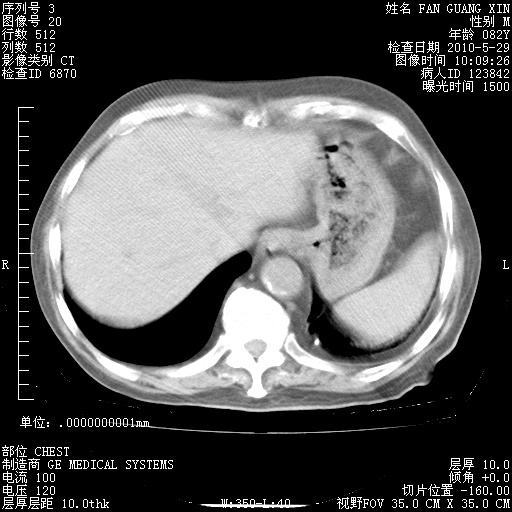

再治疗10天后的肺部CT

再治疗10天后的肺部CT 纵膈窗

阅读此次胸部CT,肺间质渗出性改变较入院时有吸收。目前从体温、白细胞、中性分叶明显增高,肯定存在细菌感染(发生医院感染哦,若无消化道及泌尿系统等感染的依据,肺部感染可能大)。若你院头孢哌酮舒巴坦钠耐药率较高,同意你的方案,若48小时体温仍高,可考虑使用碳青霉稀类抗菌药物,同时可予超声雾化、注意滴数时加大液体量。白蛋白33.30g/L较低哦,需加强营养等支持治疗。